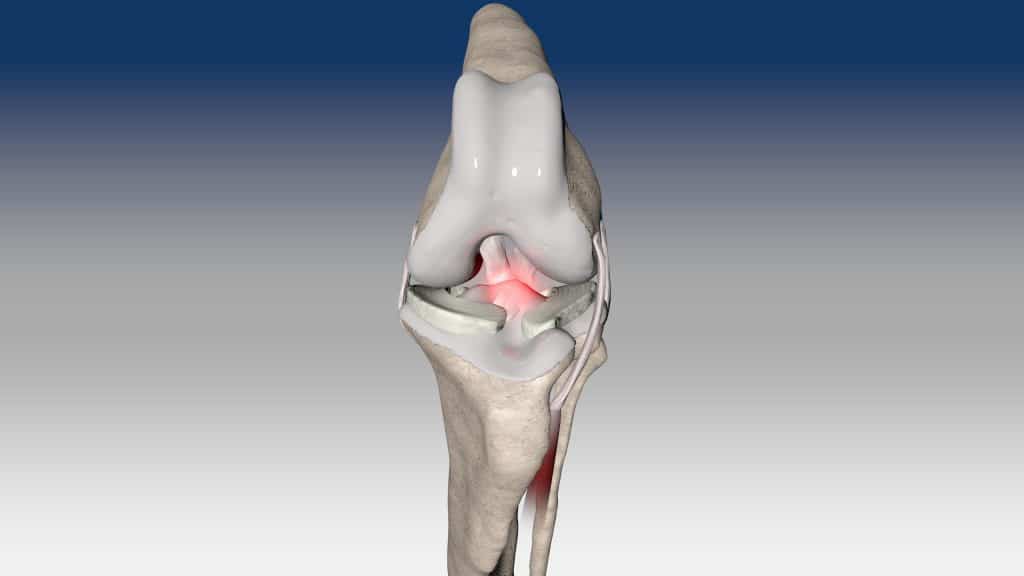

Ruptura kraniálního zkříženého vazu je hlavní příčinou ortopedických konzultací u psů. Tento stav se obvykle léčí chirurgicky pomocí osteotomických technik, mimokloubní stabilizace nebo intraartikulární rekonstrukce.

V případě ruptury kraniálního zkříženého vazu umožňuje ExtraTape® extraartikulární rekonstrukci co nejblíže izometrii původního vazu, čímž rychle a trvale stabilizuje koleno bez uzlů a zvlnění, což je slabina tradičnějších technik extraartikulární stabilizace. Ty jsou zde nahrazeny pevným ukotvením kosti pomocí interferenčního šroubu.

Řešení, které respektuje původní anatomii, obnovuje funkci postiženého vazu a je dostupné v rámci otevřené nebo artroskopické chirurgie.

V případě zkřížených vazů umožňuje intraartikulární rekonstrukci v izometrických bodech připojení, čímž obnovuje biomechaniku kolene a všechny funkce natrženého vazu.